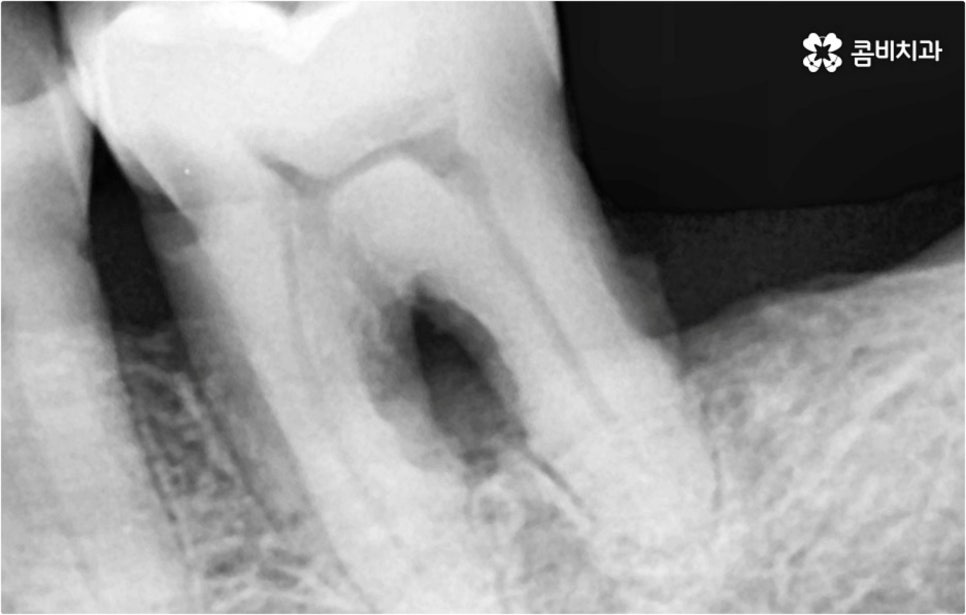

예를 들어 사고를 통해 한꺼번에 여러 개의 치아가 부러지거나 빠진 경우 연령 또는 전신 질환 여부 등을 살펴보고 치조골 상태가 양호하다면 보다 빠르고 간편한 당일 식립 방식을 이용해 볼 수 있어요. 그러나 하나 둘씩 치아가 빠질 때 마다 제때 치료를 해 주지 않아 치료 시기를 놓치고 결과적으로 무치악 상태에 이른지 오래 된 경우 또는 틀니를 오래 착용하여 잇몸뼈가 이미 많이 내려앉은 경우라면 바탕이 되는 잇몸뼈를 보충해 준 후 식립을 진행하는 방식을 이용해야 할 거예요.

또한 상악동과의 거리가 짧다면 거상술을 선행해야 할 수도 있고 심각한 치주 질환이 원인이라면 이를 먼저 깨끗하게 치료해 준 후 식립을 진행해야 성공률 또는 지속률이 높아질 수 있어요.

또한 이를 위해서 치아 주변 조직과의 거리나 잇몸뼈 높이, 밀도 등을 정확하게 파악할 수 있도록 도와주는 3D CT와 같은 정밀 진단 장비를 갖추고 환자분들의 상황에 맞는 계획을 세워 무리하지 않게 진행할 수 있는 체계적인 시스템을 운용하는 치과에서 임플란트 시술을 받으실 필요가 있어요. 만약 치과내 자체 기공소를 갖추고 있다면 보철물 제작에 대한 피드백이 보다 빠르게 전달, 반영될 수 있어 환자분들이 이용하시기에 좀 더 편안하실 거예요.